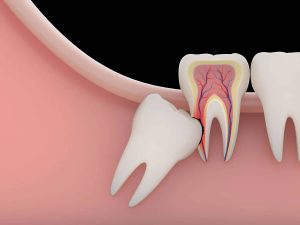

Yirmilik dişin diş eti içinde kaldığı ve diş köklerinin de çene kemiğinde gömülü halde olduğu vakalarda dişin tek parça halinde çıkarılması mümkün değildir. Bu vakalarda dişin çekilmesi gerekir. Böyle durumlarda;

- Çekilecek dişin çevresi lokal anestezi ile uyuşturulur.

- Diş eti açılır ve gömülü diş birkaç parçaya ayrılarak çekilir.

- Diş çekiminin ardından bölge temizlenir.

- Bölge temizlendikten sonra diş etine kendiliğinden eriyen materyallerle dikiş atılır.

- Ameliyatın süreci dişin yapısına bağlı olarak değişiklik gösterir.